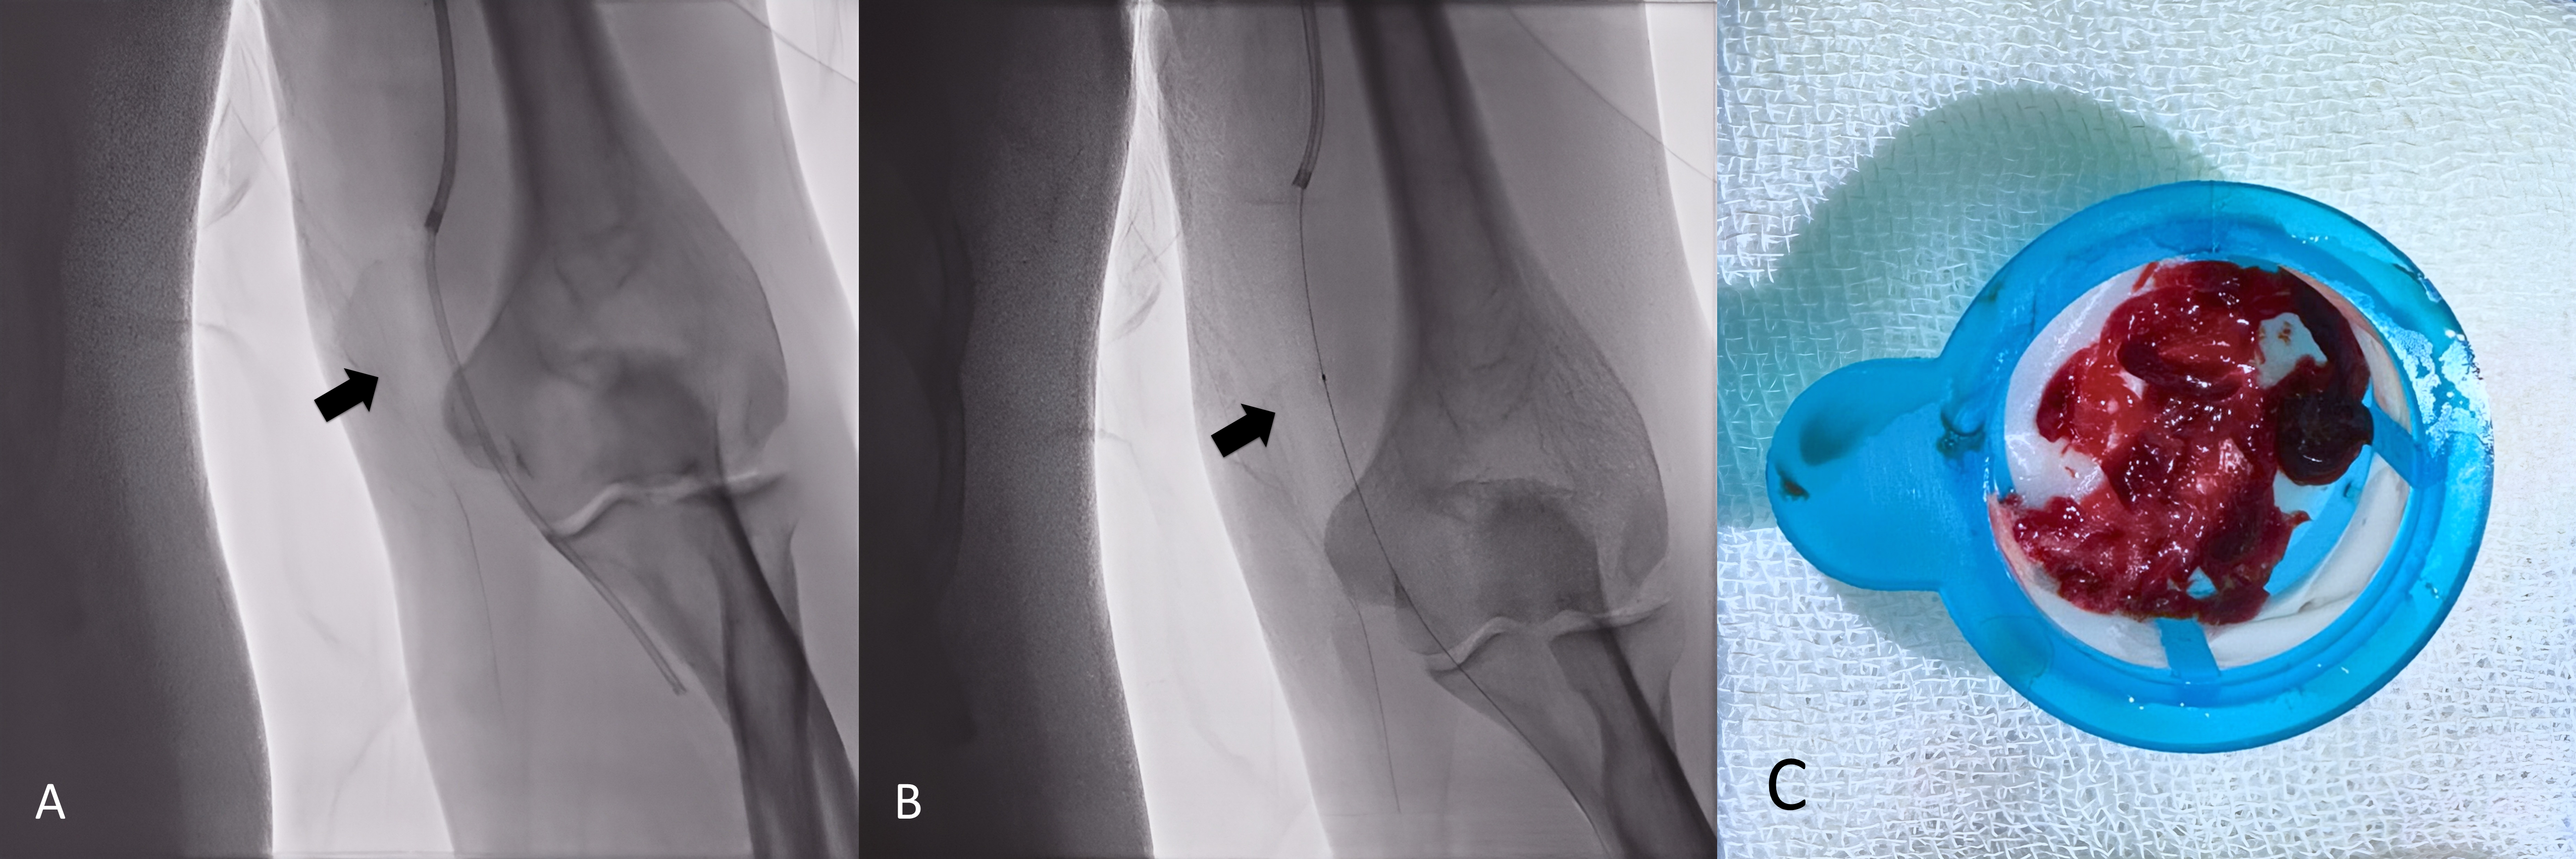

Interventions utilized a 6 Fr JR 3.5 guiding catheter via the left femoral artery, avoiding double-puncture access to minimize bleeding. Simple manual thrombus aspiration employed a 7 Fr Thrombuster II and 5 Fr Heartrail II ST01 for efficient removal. Catheter-directed thrombolysis employed alteplase (initial 4 mg bolus, followed by 1 mg/h over 24 hours) delivered directly into the thrombus via coronary thrombosuction or a guiding catheter (Figure 5-6.A), tailored for renal function preservation, with <20 mL of contrast used in one case. Serial angiography confirmed successful restoration of brachial, radial, and palmar arch flow, with TIMI-3 grade patency (Figure 5-6.B), with thrombus particles collected after thrombus retrieval (Figure 5-6.C). Only minimal transient bleeding occurred in the elderly case. Both patients were discharged on appropriate oral anticoagulation.